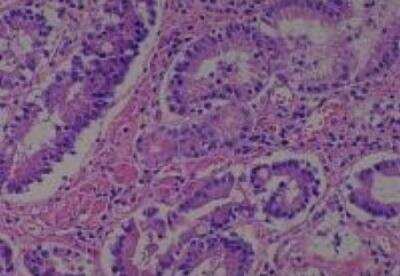

Hematoxylin & Eosin Stain: Human Common Tissue MicroArray (Normal Adjacent) [NBP2-30215] - 01. Stomach